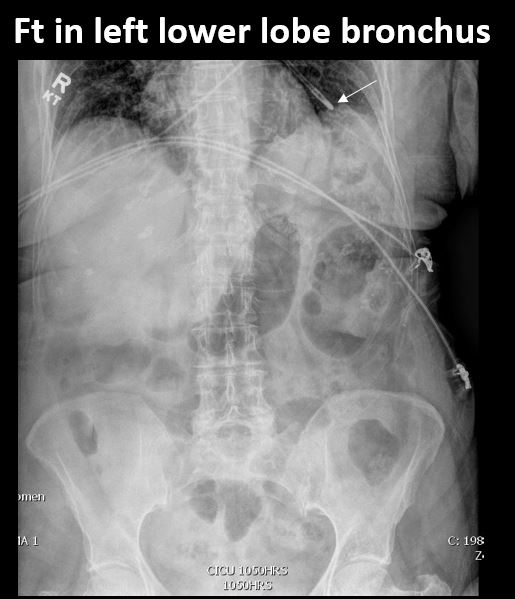

There is a FT in place and the tip of the FT is properly located at the ligament of Trietz, and is NOT otherwise malpositioned. [Yes/No]